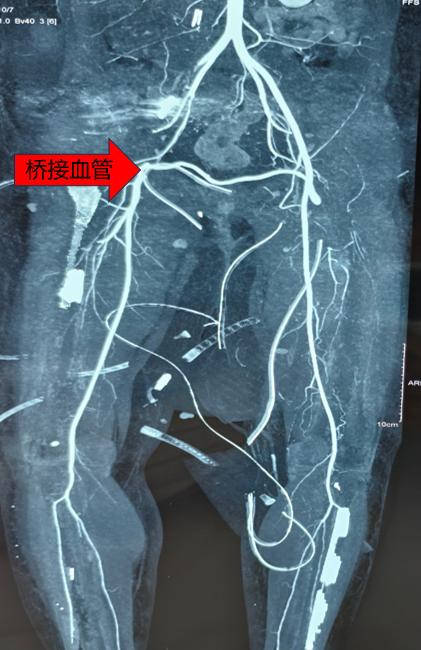

“既然无法直接吻合,我们就重建一条血液通路。”骨科樊俊俊副教授与手术团队经过多轮讨论后,决定采用“桥接血管移植技术”实施保肢。该技术核心在于取材患者自身功能相对次要的血管(如大隐静脉),作为“桥梁”,从健侧大腿引出一条血管跨越下腹部,为伤肢构建血液供应通道。

在手术显微镜高倍放大下,手术团队以极细缝线,将移植血管与健康动脉两端进行精准吻合。过程中不仅需要应对血管吻合的技术挑战,还需同步处理骨盆骨折及多处软组织撕裂伤,对团队的技术储备与团队协作提出严峻考验。

在毕龙副主任医师的指导下,手术团队历经数小时精细操作,随着血管夹开放,鲜红血液经重建的“生命之桥”流入右下肢,足背动脉恢复搏动,成功保肢。术后,在ICU与护理团队的密切监护及康复指导下,杨女士右下肢血运逐步稳定,肤色与温度恢复正常,创面愈合良好。目前已开始早期功能锻炼,生活质量获得显著改善。